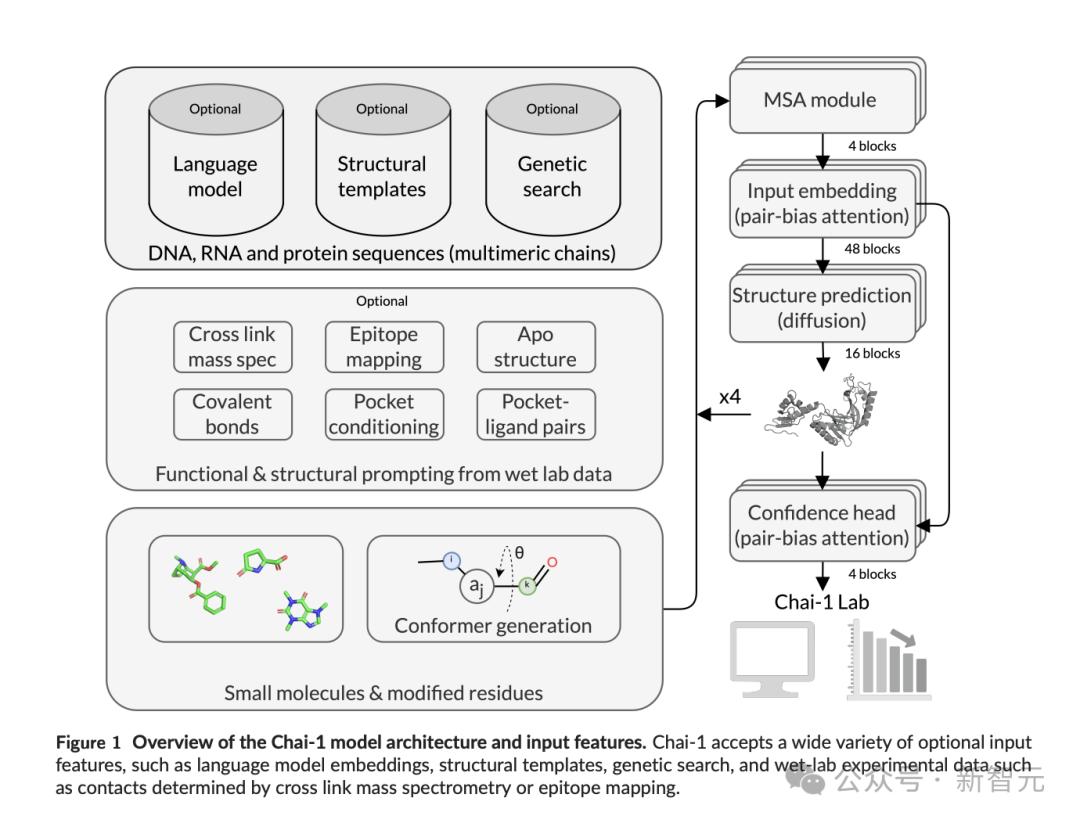

技术报告中提到,模型架构和训练策略大体依照了AlphaFold 3的论文,但有一个关键区别:

他们使用截止到2021-01-12的所有数据,仅训练了单个模型,而非针对不同的评估分别训练,此外还添加了一些新的功能。

与大多数需要MSA(多重序列比对)的结构预测工具不同,Chai-1可以在没有MSA的情况下以单序列模式运行,同时达到相近的性能。

除了利用序列信息,Chai-1也是一个「原生多模态模型」。

除了直接从序列信息进行建模的能力外,它还可以通过prompt接受新数据,例如实验得出的结合袋(pocket)、接触点(contact)和对接(docking)的约束条件。

这些约束条件能捕捉到复合物中不同物质在不同粒度上的相互作用信息,和结构模板提供链内距离的作用类似,但更注重提供链间距离的信息。

对比实验中发现,提供约束条件后,甚至可以为模型性能带来两位数的提升(图4A);但为了防止模型过于依赖约束条件导致过拟合,训练时对这些特征采用了dropout。

比如表位的约束——即使只有少量的接触点或结合袋残基的信息,也能使抗体-抗原结构预测的准确率翻倍,让AI在抗体工程中的角色变得更加实用。